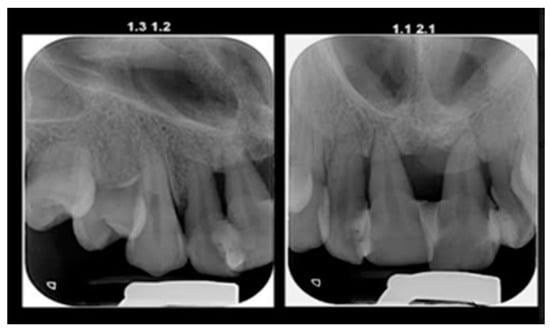

A 15-year-old female teenager was referred by a general practitioner to the Department of Periodontology, Faculty of Dental Medicine, University of Medicine and Pharmacy Carol Davila, Bucharest, Romania. There were no other diseases, such as diabetes or other hematological disease, no smoking, and no medications being taken by the patient. She had an accident (falling down the stairs) when she was 7 years old but did not experience any general or dental trauma (without notable objective or subjective clinical signs) as a result. Consequently, she did not visit a dentist for any treatment. The reasons for the first visit were teeth mobility, which appeared 2 years behind, poor aesthetic aspect of gingiva, and poor masticatory performance. The following clinical parameters were assessed at baseline: bleeding upon probing (BOP), plaque index score (O’Leary et al.) [12] and probing depth (PD). All measurements were performed by the same examiner using a periodontal probe (North Carolina 15 mm probe) on six sites for each tooth. The initial examination revealed deep probing pocket depth, severe gingival overgrowth, bleeding upon probing, and gum recession. Gingival inflammation was observed. Periodontal abscesses were registered to both maxillary central incisors (Figure 1). Suppuration and tooth mobility were registered to both maxillary central and lateral incisors. Gingival overgrowth was registered mainly on the maxillary anterior tooth side.

Figure 1.

Clinical aspects before periodontal treatment: (a) frontal aspect, (b) right lateral aspect, (c) left lateral aspect, (d) maxillary occlusal aspect, and (e) mandibular occlusal aspect.